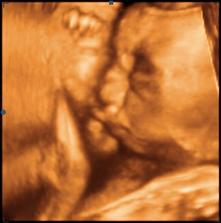

*21.12.2009 ... 19+5 tt, velký UTZ ve 20tt (mimi odpovídá 19+4tt, vše v pořádku!, dozvěděli jsme se pohlaví)